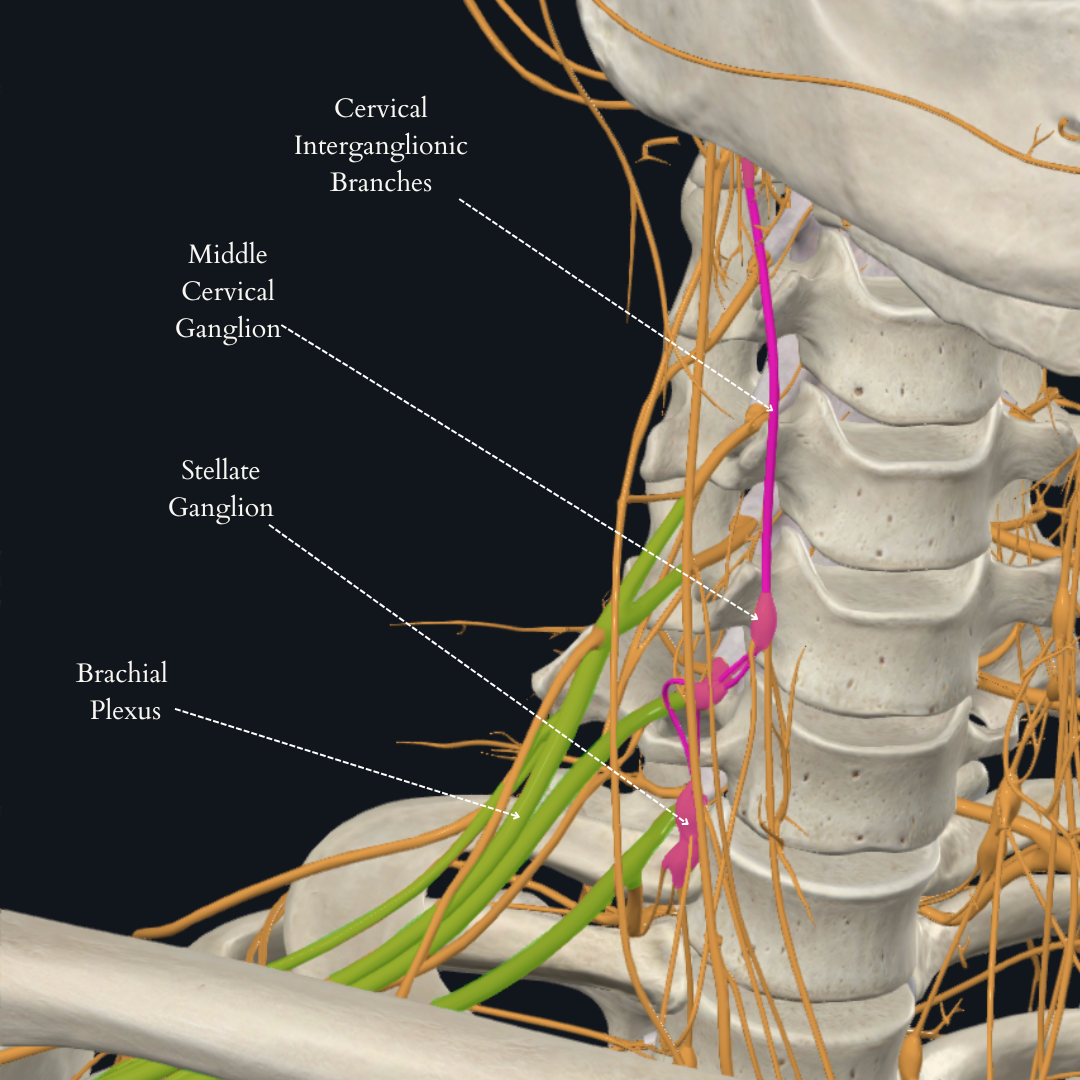

Coverage: Brachial Plexus – Roots level

Considerations: Inferior trunk (C8-T1) is usually spared unless specifically targeted. This trunk corresponds to the ulnar nerve and its consequent coverage. Large volume local may spread to epidural space, phrenic nerve (hemidiaphragmatic paralysis); dorsal scapular nerve (winged scapula and impaired ability to elevate arm above the horizontal) or long thoracic nerve injury (winged-scapula). This is why Feigl et al advocate for an OOP technique, though they also caution to be mindful that the vertebral artery may be very superficial.

The posterior approach is considered the safest since the major vessels, nerves and sympathetic ganglia are anterior. It is also popular for ease of approach. In the classical approach, the ultrasound probe is placed over the sternocleidomastoid muscle at the level of the cricoid cartilage (transverse process of C6), between the anterior and the middle scalene muscles until the roots of C5, C6, and C7 are identified as three round hypoechoic spheres “traffic light sign”.

A common way to confirm the correct sonoanatomy is to place the probe in the supraclavicular fossa to identify the subclavian artery and the brachial plexus in what is referred to as the “bundle of grapes” sign. The probe is then translated in a cephalad direction keeping the nerves in view until the roots of C5, C6, and C7 are identified between the anterior and middle scalene muscles. A paper by Franco et al suggests that while the “traffic light sign” usually has 3 “lights,” they may in fact be made up of only 2 nerves (C5 and a split C6). The important clinical implication is that “an injection attempted between what is commonly perceived as the gap between C6 and C7 would indeed be an intraneural injection at C6, which could potentially spread toward the neuraxial space.”

Another common way to identify the Brachial Plexus at the level of the Interscalene Groove is to trace the anterior rami of individual cranial nerves. As mentioned above, this may help identify instances where the three visible nerve roots are actually C5 and a split C6 (as captured in the video below!)